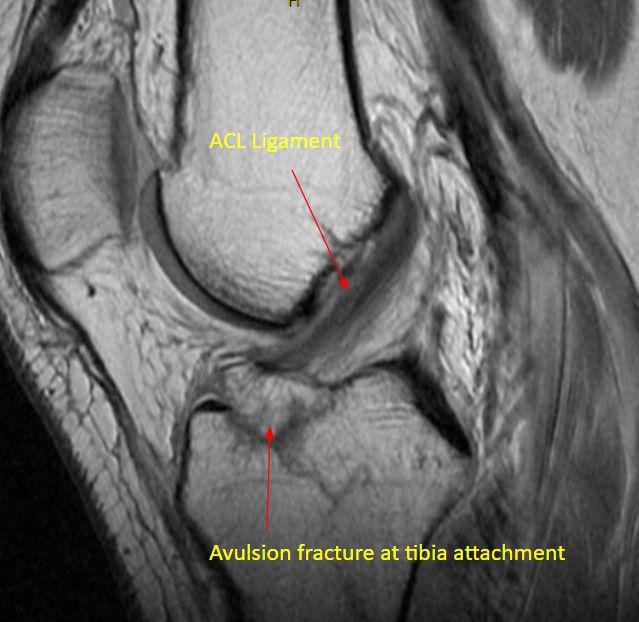

Dr. Pancio studied my daughters MRI before he came in and talked to us. He examined her knee and told us that her exam confirmed what he had found on the MRI which was missed by the radiologist. He prescribed the appropriate physical therapy and my daughter is on her way to making a full recovery without surgery! If she would have needed surgery, we have full confidence that Dr. Pancio would be great! He is very observant and knowledgeable. He explained everything that is going on with her knee also why and when it would hurt in different situations.